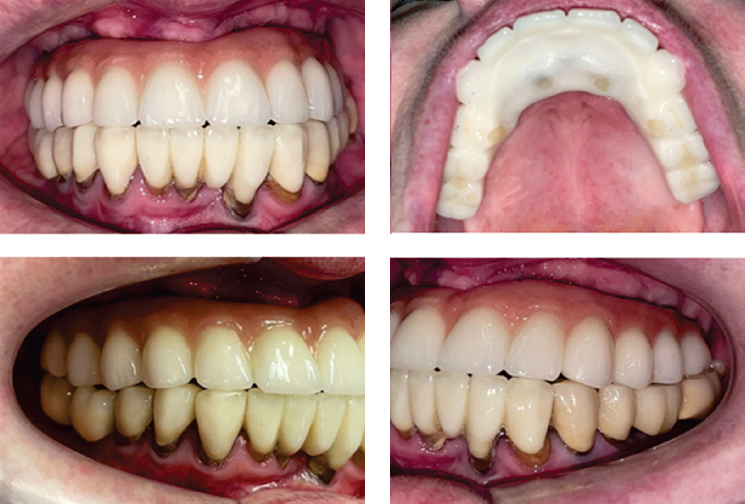

Принято решение для контроля окклюзионных контактов изготовить прототип постоянных коронок из фрезерованной пластмассы, зацементированный на титановой балке (рис. 21, 22).

Рис. 21. Прототип постоянных коронок на титановой балке

Fig. 21. Prototype of permanent crowns on a titanium beam

Рис. 22. Прототип постоянных коронок в полости рта

Fig. 22. Prototype of permanent crowns in the oral cavity

На рисунке 23 изображена постоянная конструкция, выполненная из диоксида циркония до соединения конструкции с титановой балкой. Затем готовая конструкция и балка соединяются цементом (рис. 24).

Рис. 23. Вид постоянной конструкции до цементировки с титановой балкой

Fig. 23. View of the permanent structure before cementation with a titanium beam

Рис. 24. Вид готовой постоянной конструкции

Fig. 24. View of the finished permanent structure

Таким образом постоянная конструкция устанавливается в полости рта (рис. 25, 26).

Рис. 25. Фотографии постоянной конструкции в полости рта

Fig. 25. Photographs of permanent structure in the oral cavity